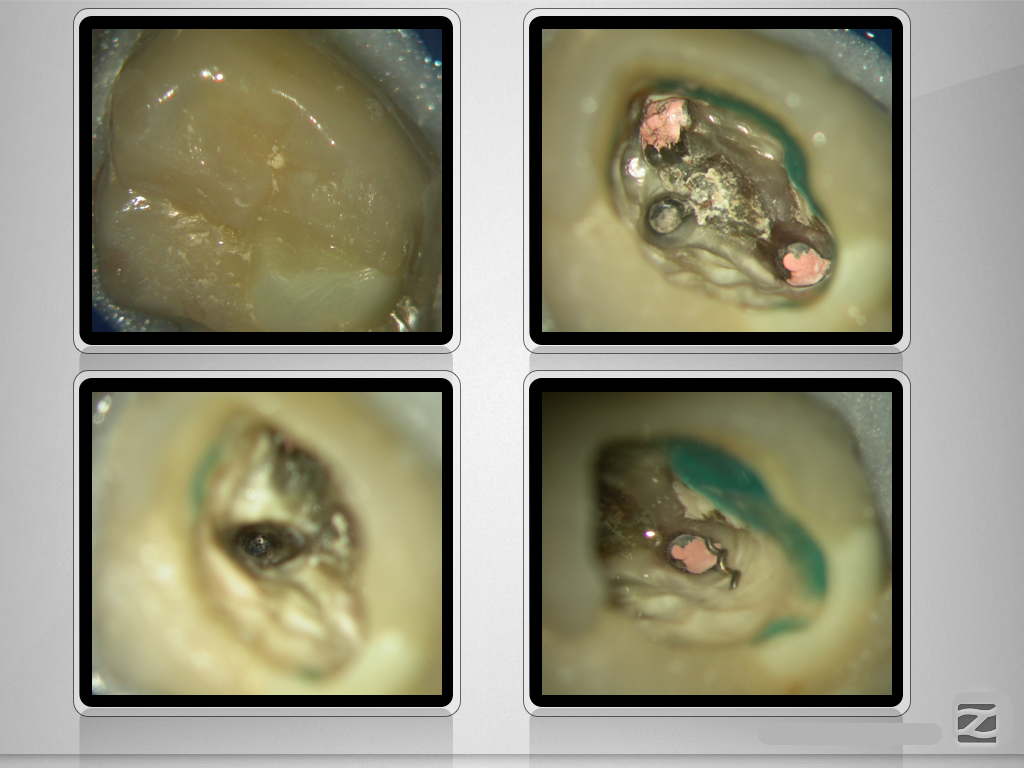

27E.007

„Navigierte“ Fragmententfernung